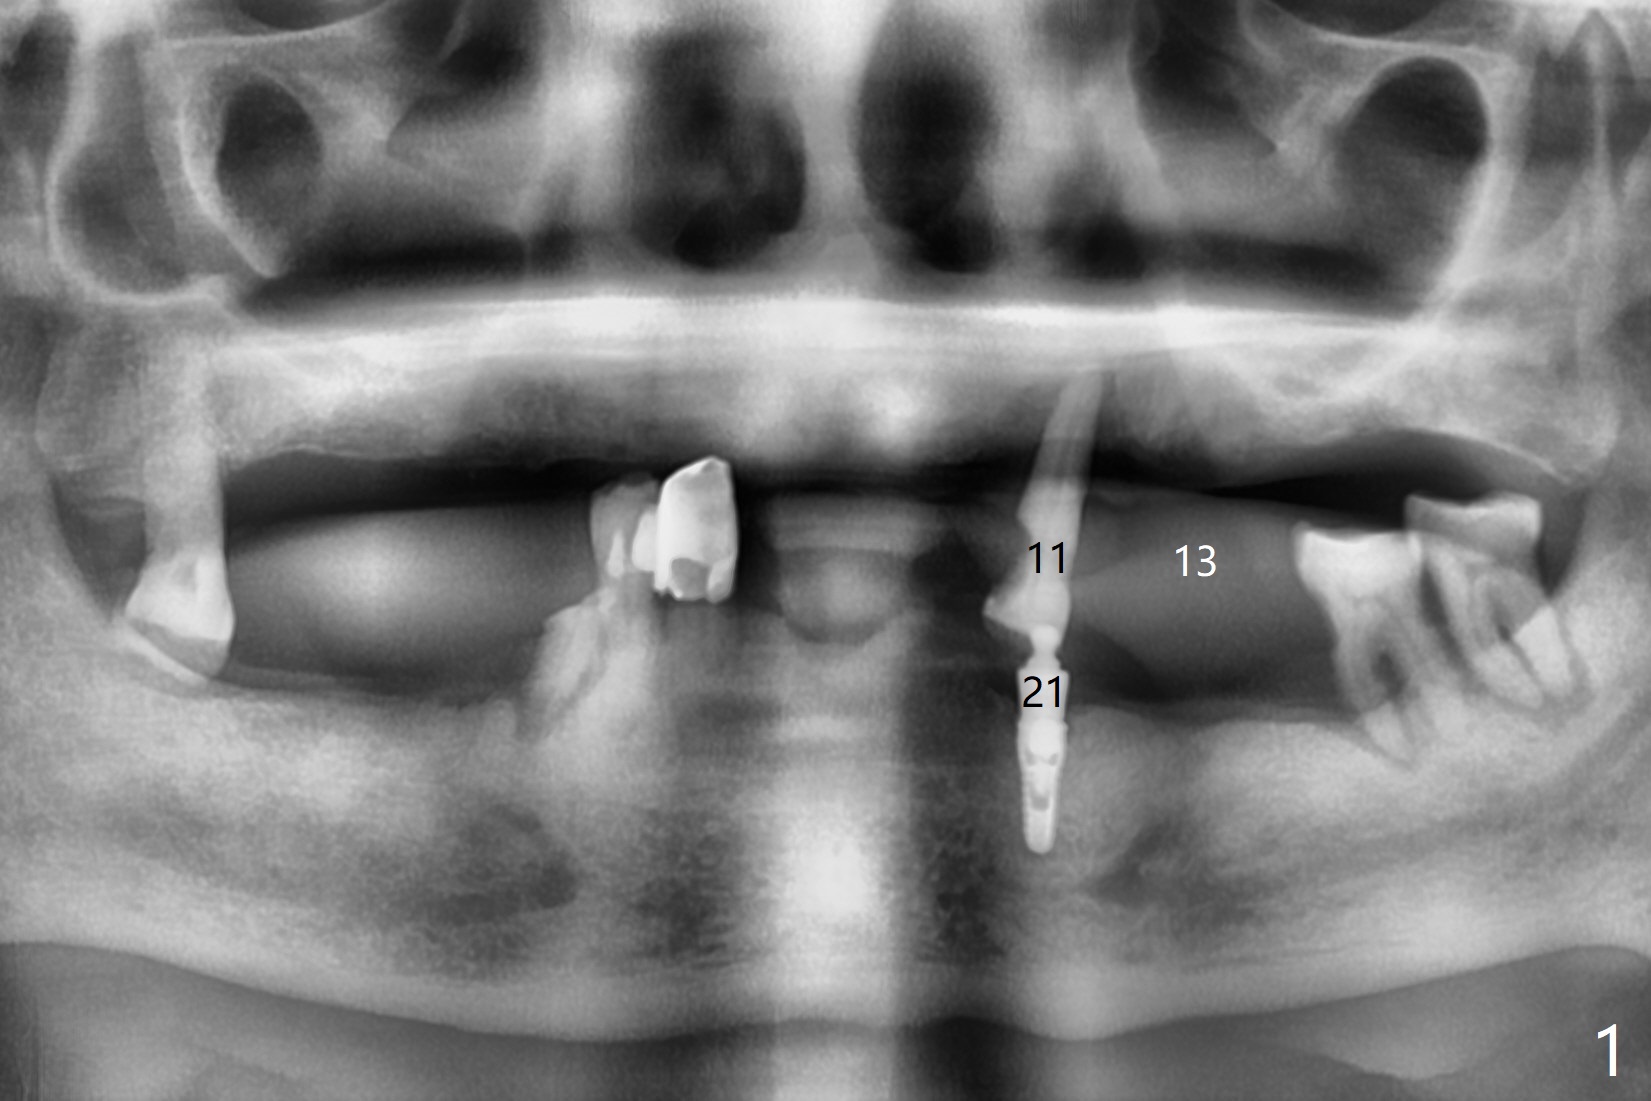

A 76-year-old man returns to clinic with chief complaint of loose top partial 2 years 3 months post #21 implant placement (Fig.1,2). The tooth #11 has mobility, while the socket of #13 heals and the tooth #1 is stable and functional (Fig.1). Two implants will be placed at #11 and 13 (Fig.3,4) with ball abutments (4 and 2 mm cuffs, respectively). Since the bone density is low at #13, bone expanders will be used as well as for sinus lift (implant 4x10 mm instead, PRF). Keep the tooth #11 as a denture one. Soft reline will be used to hold the abutments.